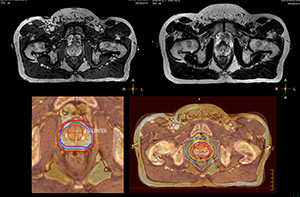

Impressive clinical benefits for prostate

“The biggest problem for CT-based planning, especially in prostate, is you can’t see the cancer very well,” says Dr. Stevens. “On CT it can be quite challenging to see the edge of the prostate especially at the apex. When the edge of the prostate can’t be delineated well on CT, radiation oncologists will increase their margins a little bit so they don’t miss it, but that can also increase toxicity.” “Using MR, the prostate is well delineated. We quickly see the edges of cancerous tumors like in prostate cancer, and as normal structures can be defined, we can optimize the treatment plan to protect these organs and their normal function. This can potentially improve the outcome. And it improves workflow as well. We can contour more quickly, confident that the tumor is going to be in the field.” “The Ingenia 3.0T MR scanner provides high resolution allowing us to make scans fast for the patients. It also gives the potential to include methods like MR spectroscopy and diffusion weighted Imaging, which we’re in the process of doing right now,” Dr. Stevens adds.

“There are some general challenges in RT imaging – even with CT – such as imaging geometry and positioning accuracy. Positioning is extremely important in RT, because we need reproducibility between imaging and treatment position. We also need accurate geometry so we can be sure our treatment plan is properly delivered during the treatment,” says Dr Yan. “The Ingenia MR-RT configuration includes an external laser positioning system for patient alignment and a flat tabletop for imaging the patient in treatment position. Ingenia MR-RT also came with a special QA package for regular monitoring of precision. Our Ingenia 3.0T scanner achieves good geometric accuracy – within a millimeter for most patients – and the phantom measurement is even better,” he adds. “Ingenia’s wide 70 cm bore is valuable to easily accommodate immobilization devices needed in RT,” says Dr. Stevens. “With a small bore MR scanner you can’t get the RT immobilization devices into the scanner properly; the large bore makes it easy to image patients in their immobilization device.”